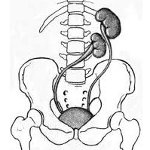

По месту расположения почки выделяют несколько видов дистопии - поясничную, тазовую, подвздошную, субдиафрагмальную (торакальную). В основе классификации лежит уровень отхождения почечных артерий от ствола аорты, который в норме должен соответствовать I поясничному позвонку.

При поясничной дистопии почки (66,8 %) наблюдается отхождение почечных артерий на участке от II-III поясничных позвонков до бифуркации аорты. При этом почка располагается несколько ниже нормального анатомического уровня. Обычно такая дистопированная почка обращена вперед лоханкой, пальпируется в области подреберья и может быть принята за нефроптоз или опухоль.

Подвздошная дистопия (11,9%) характеризуется отхождением аномального количества почечных артерий от общей подвздошной и расположением почки в подвздошной ямке. Пальпторно такая почка иногда ошибочно принимается за кисту яичника или объемное образование брюшной полости.

В случае тазовой дистопии (21,3 %) почечные артерии ответвляются от внутренней подвздошной, в связи с чем почка оказывается расположенной между прямой кишкой и мочевым пузырем у мужчин или прямой кишкой и маткой у женщин. Мочеточник у такой дистопированной почки всегда укорочен. Смещенная в полость таза почка ошибочно может приниматься за гематометру, воспалительно измененный придаток при аднексите, внематочную беременность.

Субдиафрагмальная (торакальная, внутригрудная) дистопия почки отмечается при отхождении почечных артерий на уровне тела XII грудного позвонка. При этом почка располагается высоко, иногда в грудной полости. Сосуды и мочеточник у торакальной почки значительно длиннее обычных. Торакальная дистопия почки может быть принята за кисту средостения или легкого, опухолевое образование, абсцесс, осумкованный плеврит.